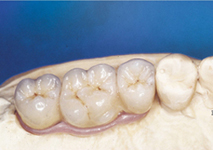

Protetické řešení může být pomocí můstku, který je kotvený na implantátech nebo pomocí jednotlivých korunek na implantátech.

V zásadě je možné do těchto můstků zařadit i přirozené zuby, zejména pokud je potřeba tyto zuby ošetřit proteticky – korunkami. Korunky nebo můstky mohou být na implantáty nacementovány nebo přišroubovány.

S pomocí zubních implantátů můžeme díky různým kotevním systémům (třmeny, kulové hlavy, Locatory) zajistit stabilitu a držení protézy nebo při použití většího počtu implantátů zhotovit pevné náhrady – můstky nalepené nebo našroubované na pevno na implantáty.

S těmito typy náhrad můžeme dosáhnout perfektní funkci, výbornou estetiku, fonetiku a současně zajistit u pacienta možnost dobré hygienickou péče a čištění, která je pro životnost implantátů velice důležitá.